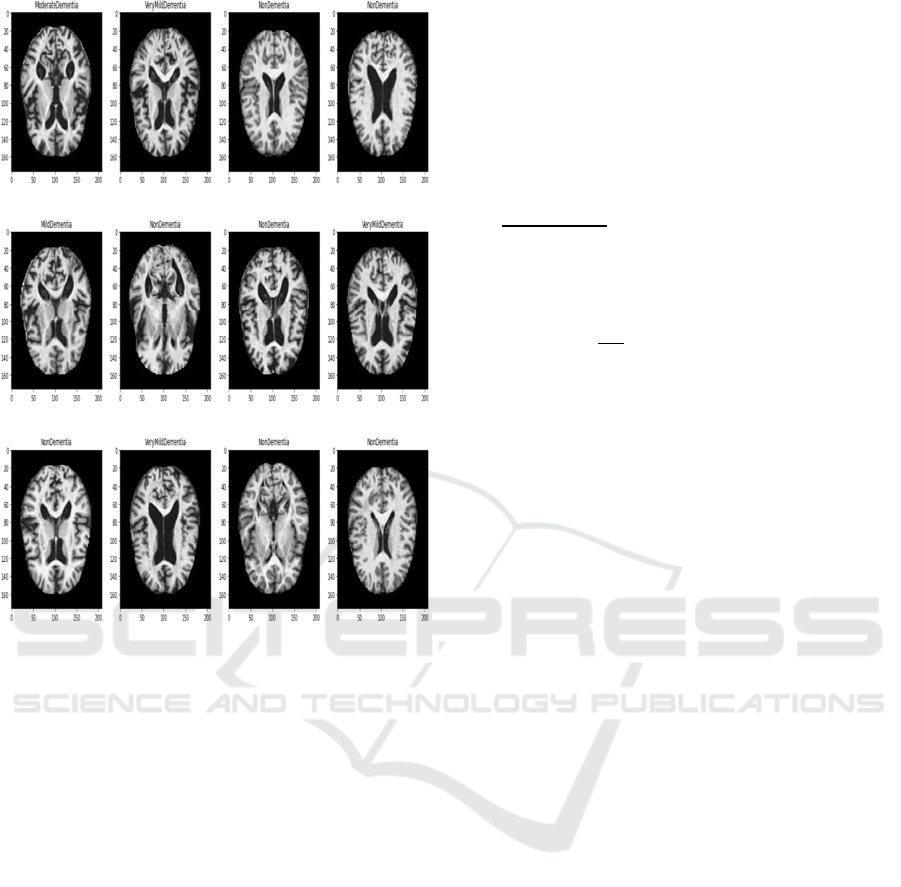

demented (Gaugler et al. 2016). Figure 1 presents

the magnetic resonance image (MRI) images of

different AD conditions. Although the MCI and

dementia patients both are experiencing a reduction

of cognitive abilities, dementia patients would suffer

from more pronounced difficulties with thinking or

hampered judgment.

Figure 1: AD presented by MRI images (a) mild dementia;

(b) moderate demented; (c) nondemented; and (d) very

mild demented.

more than 2,000 MRI images. The dataset outcome of

four categories of MR images has presented in Figure

3.

Figure 3: Dataset outcome of different dementia stages

(3*4 image matrix).